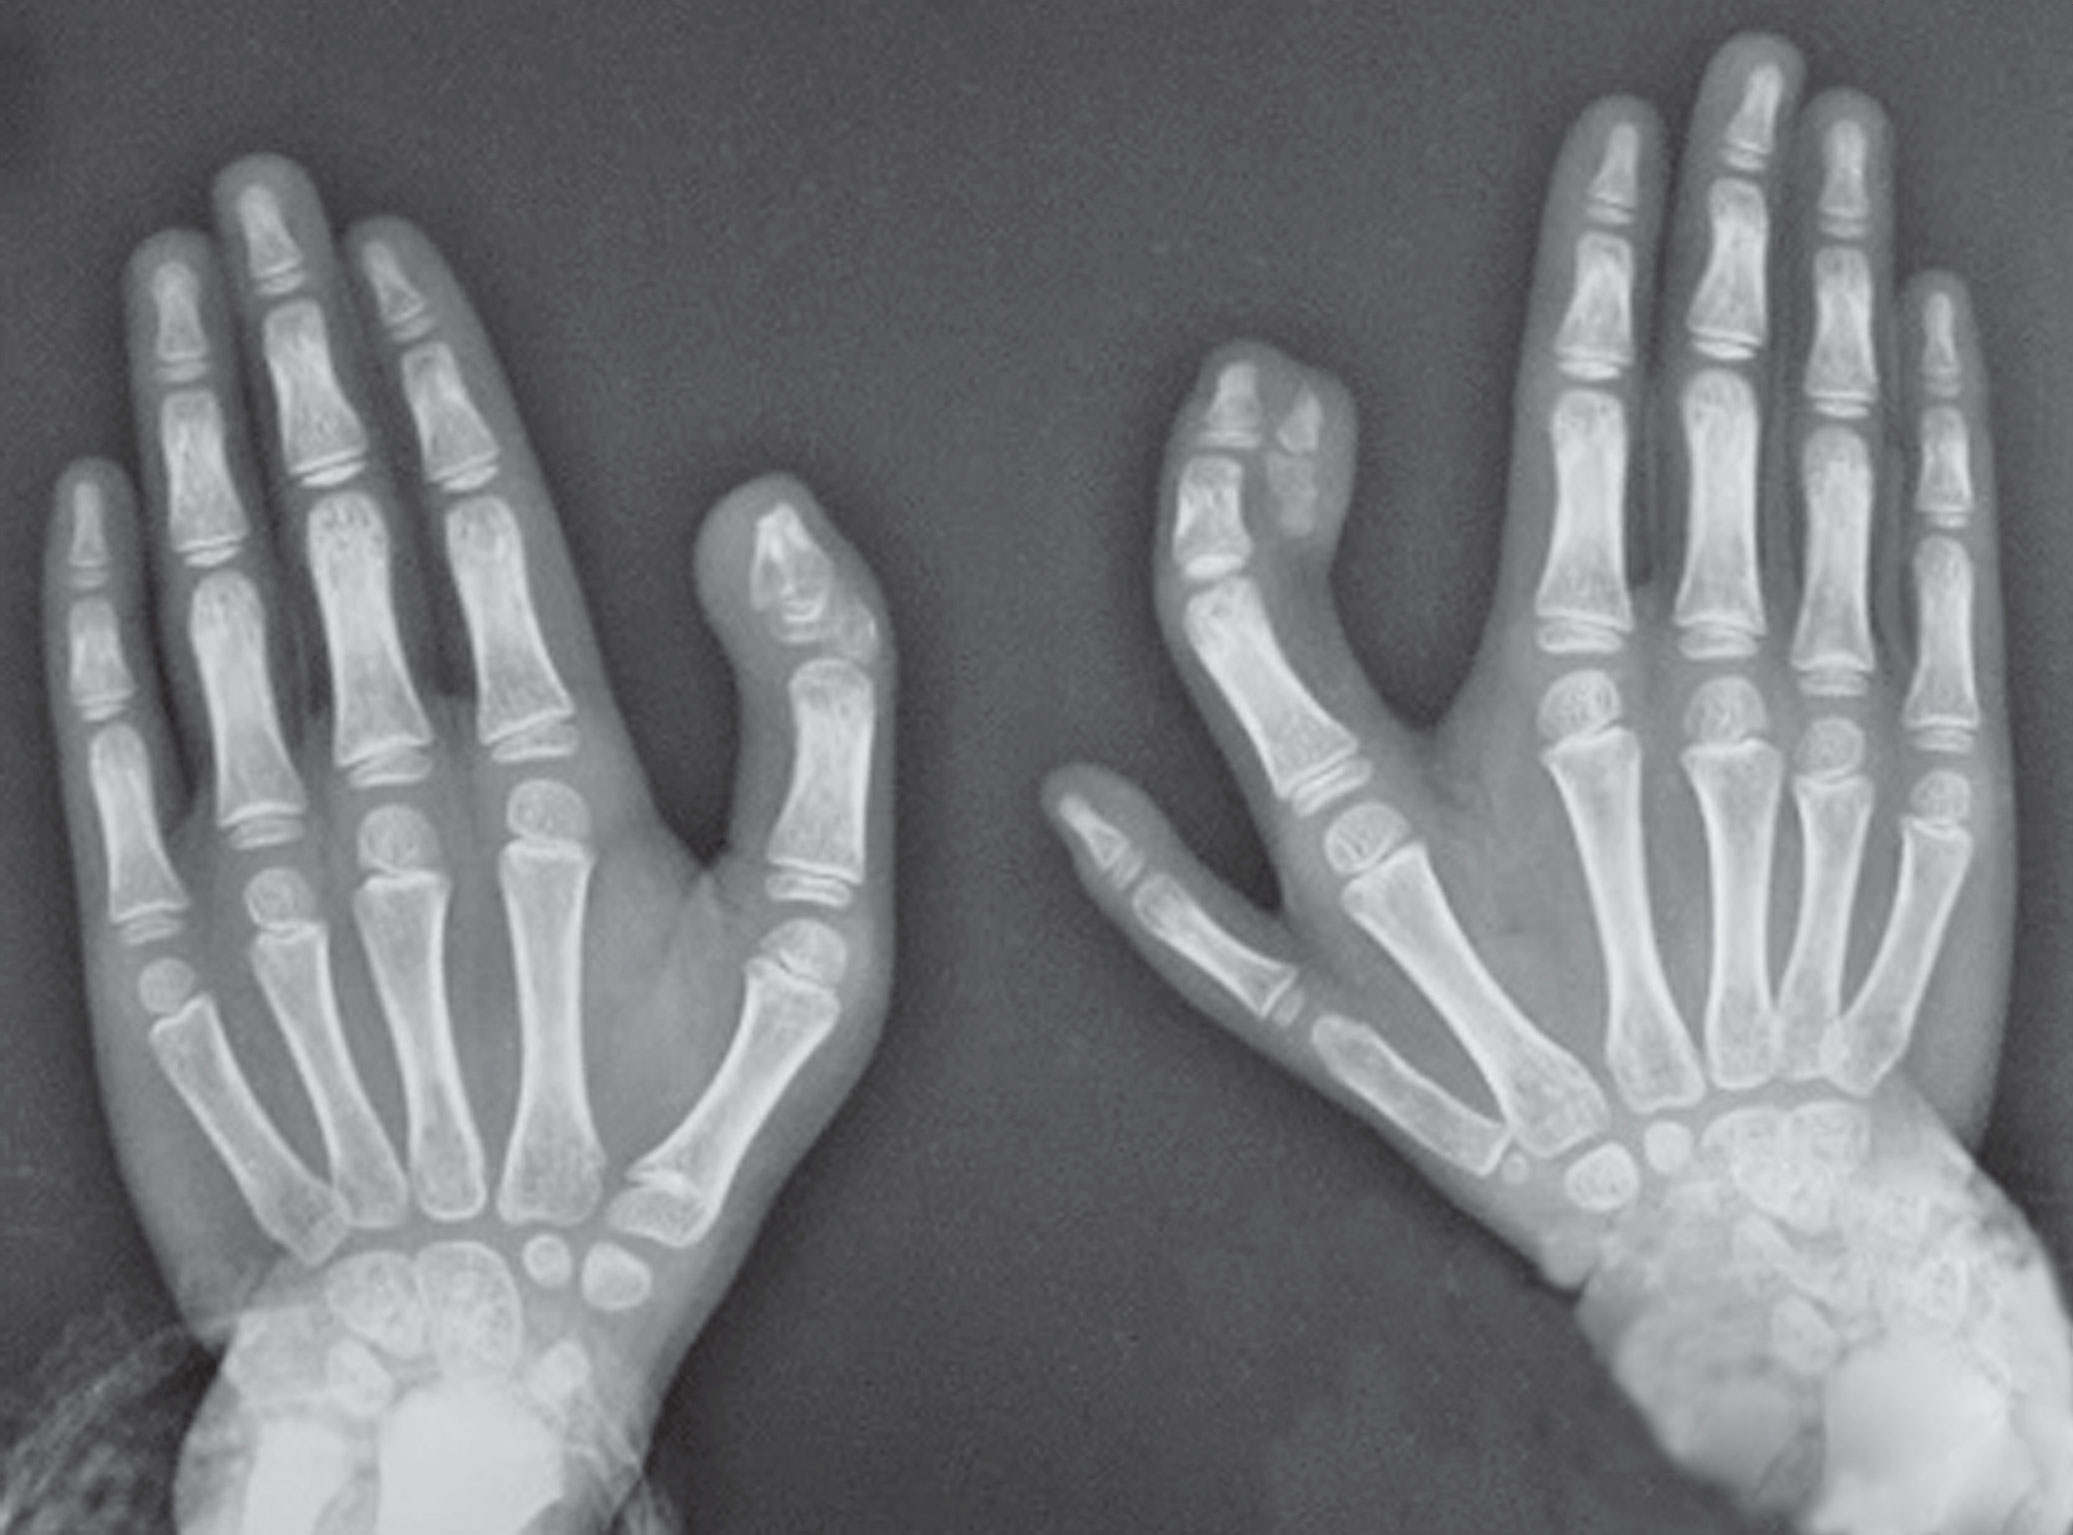

图2-3-10 骨关节严重畸形中央型多指病例2

A.右侧中央型多指并指;B.X 线片显示多指发出自中指近节,近节指骨在近端融合,其近节指骨中远段以远分别与示指、环指并连,其中中、环指末节指骨融合,应切除骨关节发育较差的一侧(桡侧)保留的中、环指并指二期行分离手术